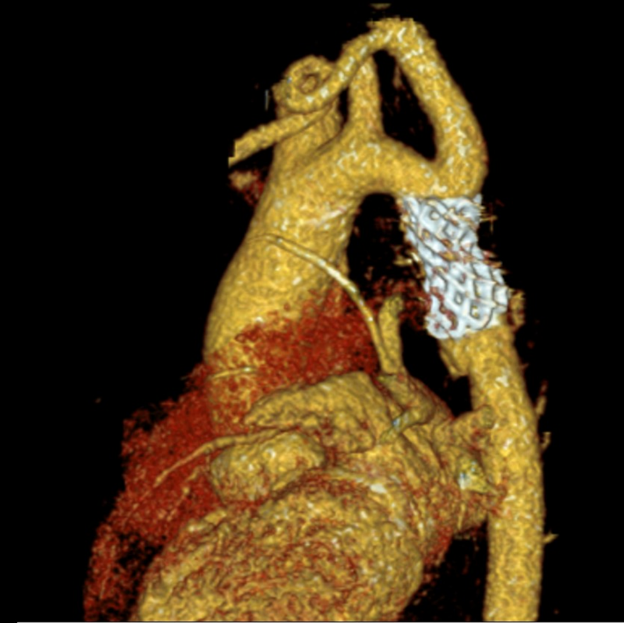

患者术后6个月复查CTA显示支架位置理想,且无并发症。

术后CTA影像

术后主动脉弓部3D打印模型